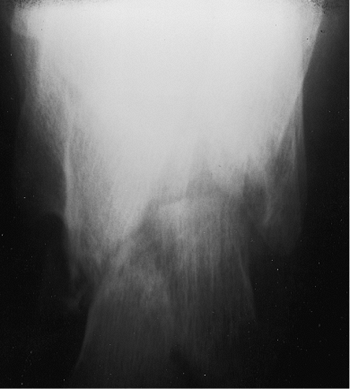

calcaneus, subtalar joint, and calcaneocuboid joint. The lateral view

of the calcaneus allows preliminary classification of the fracture and

information about the integrity of the posterior facet (Fig. 35.1).

Figure 35.1.

The lateral view of the calcaneus demonstrates a joint-depression fracture with a portion of the posterior facet impacted into the cancellous bone of the tuberosity. The sagittal plane rotation of the displaced posterior facet is best seen on this view. |